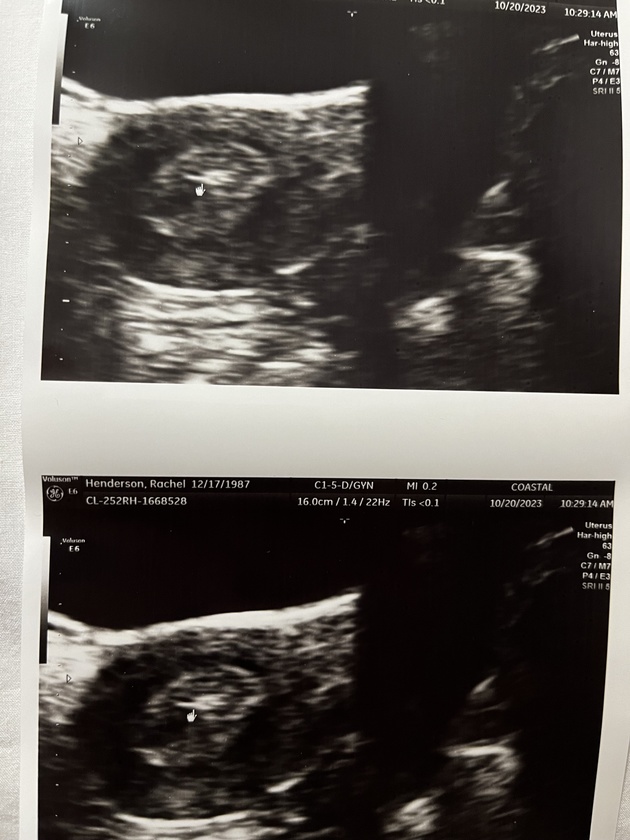

The ultrasound arrow shows where the embryo was placed in my “Olympic uterine lining” ( doctor quote!) Usually they want the uterine lining to be 6mm and mine was a healthy 11.6 mm.